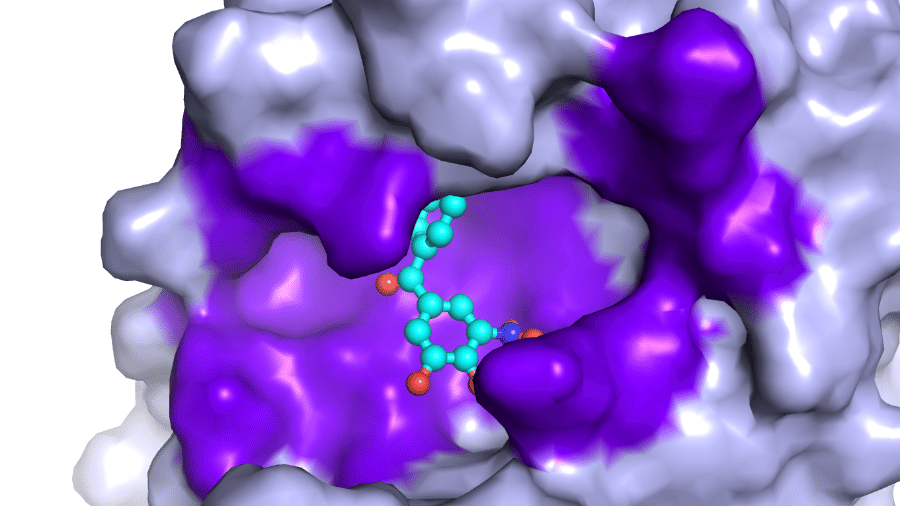

Muito antes do primeiro caso oficial de coronavírus surgir no Brasil, cientistas do país já buscavam uma cura ou um tratamento. Desde o fim de janeiro, pesquisadores do Cnpem (Centro Nacional de Pesquisas em Energias e Materiais), em Campinas (SP), investigam medicamentos que podem ajudar quem adoeceu de Covid-19. Menos de dois meses depois do início dos testes, que envolveram mais de 2.000 candidatos a tratamentos, restaram cinco opções consideradas as mais promissoras. Começa agora uma nova fase de testes.

O Cnpem, onde a maior parte da pesquisa é feita, é um centro independente de pesquisas, mas supervisionado pelo MCTIC (Ministério da Ciência, Tecnologia, Inovações e Comunicações). Ele conta com laboratórios nacionais de nanotecnologia, biociências, biorrenováveis e de luz síncrontron, sendo este último o responsável por um dos mais avançados aceleradores de partículas do mundo.

A busca por um medicamento envolve o “reposicionamento de fármacos”. O que é isso? Eles selecionam medicamentos que já estão nas prateleiras das farmácias, portanto já aprovados para uso humano. Dos 2.000 iniciais —eram analgésicos, anti-hipertensivos, antibióticos e diuréticos, entre outros— o número caiu para 16 que tiveram resultados promissores e, posteriormente, para cinco medicamentos mais promissores, baratos e disponíveis no mercado brasileiro.

O estudo brasileiro começou com quatro pessoas, passou para seis e agora são 11 no projeto. Em tempos de isolamento, apenas pesquisadores ligados ao coronavírus estão seguindo o trabalho direto no Cnpem, enquanto outros ficam de home office. Aliás, o distanciamento social é um dos desafios para descobrir o medicamento correto.